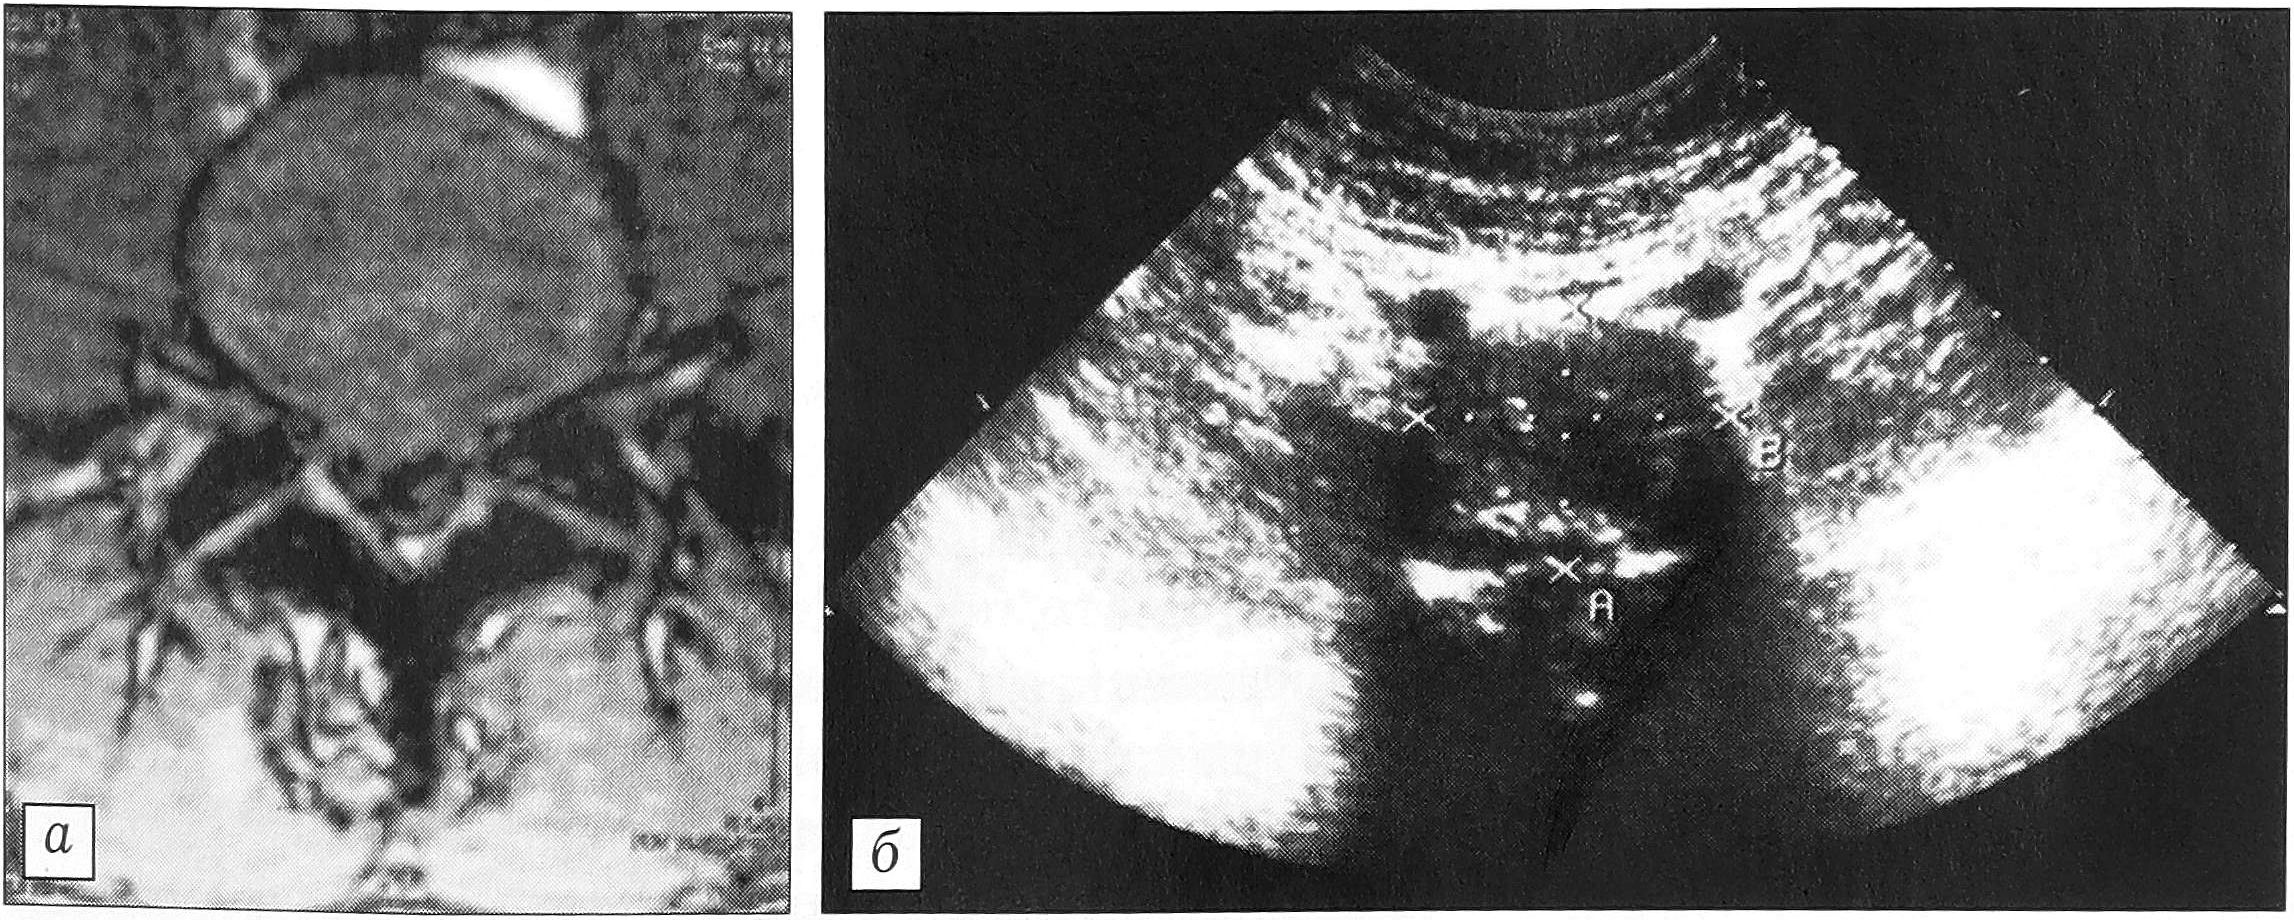

Фиброзное кольцо с четким контуром, без дополнительных эхо-сигналов в толще выявлено в 57 межпозвонковых дисках. На появление дистрофических изменений указывали уплотнение его внутреннего контура, слоистость. В 13 дисках отмечены утолщение или двухконтурность фиброзного кольца. Согласно исследованиям А.Ю. Кин- зерского [6], это свидетельствует о нестабильности в данном сегменте. В 18 случаях фиброзное кольцо было деформировано при сохранении его структуры, что обусловливалось смещением пульпозного ядра с образованием протрузии (рис. 1). Истончение и разрыв фиброзного кольца (локальные гиперэхогенные сигналы в его толще) свидетельствовали о наличии грыжи. Последняя выявлена в 6 случаях: в одном —центральная, в трех —- парамедианная (рис. 2) и в одном — заднебоковая.

Рис. 1. Протрузия межпозвонкового диска. а — МРТ в аксиальной проекции; б — ультрасонограмма той же больной: определяется расширение границ фиброзного кольца.

Рис. 2. Грыжа диска. а — МРТ в аксиальной проекции; б — ультрасонограмма того же больного: определяется разрыв фиброзного кольца.